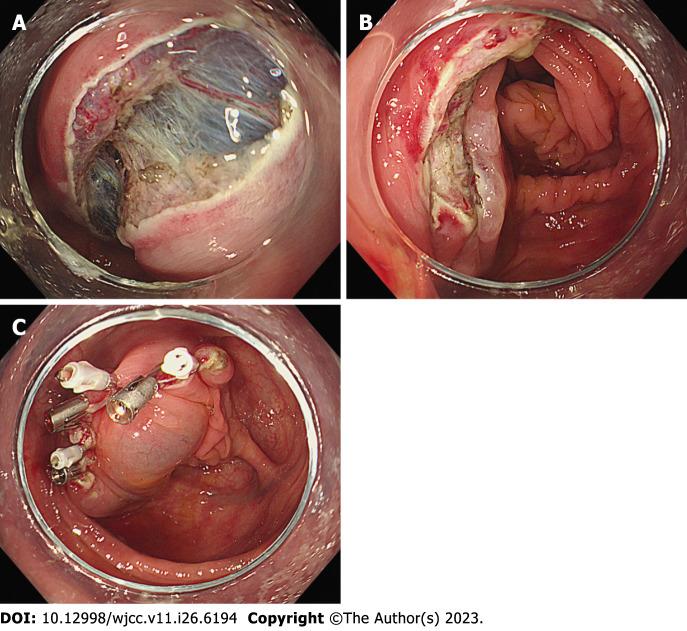

A 78-year-old man underwent colonoscopy for colorectal cancer screening. During colonoscopy, a yellowish submucosal tumor with positive cushion sign was observed in the ascending colon measuring about 4.5 cm. A nodular mucosal lesion of about 2.5 cm was observed on the mucosal surface of the lipoma. The lipoma was so large that it occupied much of the inside of the colon, making it difficult to see the entire laterally spreading tumor (LST) at once. The LST was confined to the surface of the lipoma, which had a semipedunculated shape with a wide neck. The margin of the LST was not observed at the neck of the lipoma. ESD was performed and the colonic lipoma with the LST was successfully removed without complications. After 3 d of hospitalization, the patient was discharged without any symptoms. The final pathology report showed that the lesion consisted of submucosal lipoma and tubulovillous adenoma with low-grade dysplasia.

一名78岁男性因结直肠癌筛查接受结肠镜检查。结肠镜检查期间,在升结肠观察到一个约4.5 cm的黄色黏膜下肿瘤,有阳性垫征。在脂肪瘤的黏膜表面观察到一个约2.5 cm的结节状黏膜病变。脂肪瘤很大,占据了结肠内部的大部分空间,使得难以一次性看清整个侧向发育型肿瘤(LST)。LST局限于脂肪瘤表面,呈半蒂状,颈部较宽。在脂肪瘤颈部未观察到LST的边缘。实施了ESD,成功切除了伴有LST的结肠脂肪瘤,无并发症发生。住院3天后,患者无症状出院。最终病理报告显示病变由黏膜下脂肪瘤和低级别异型增生的管状绒毛状腺瘤组成。